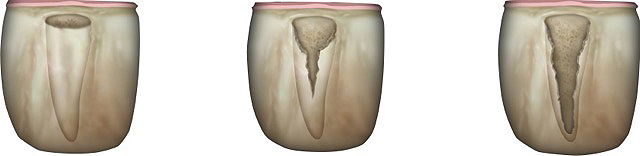

Grade I sockets are the most ideal. Following tooth extraction, a socket that has an intact buccal plate, adequate interproximal bone, and satisfactory apical topography will fall into this category. In this classification, an intact buccal plate is defined as having no fissures or dehiscences and less than 25% loss of height (Figure 4, left; Figure 5, left). This percentage of buccal plate loss was selected as the cutoff based on the average root length of single-rooted teeth, which is 14.2 mm,25 and the amount of buccal plate that can be reliably regenerated during immediate implant placement. Adequate apical topography is defined as enough bone present apical to the extraction site to allow for engagement of 3 mm to 4 mm of a properly positioned immediate dental implant (Figure 2).1,2 Adequate interproximal bone is defined as no or mild (up to 2 mm) periodontal bone loss on the adjacent teeth as to allow for support of the interproximal soft tissue and to enable placement of the platform of an immediate implant in the proper apical-coronal position relative to the adjacent teeth while still being bordered by bony walls on the mesial and distal aspects26 (Figure 3, left).

Grade II sockets are differentiated from Grade I by the amount and quality of the remaining buccal plate. A Grade II socket has a fissure, dehiscence, or deficiency of the buccal plate totaling a 25% to 50% loss. Like Grade I sockets, they have adequate interproximal bone and apical topography (Figure 3, left; Figure 4, center; Figure 5, center).

Grade III sockets are the most deficient and include any socket with inadequate apical topography, insufficient interproximal bone, or more than 50% loss of buccal plate. Inadequate apical topography is defined as not enough bone present apical to the extraction site to allow for implant placement and may be the result of bone loss caused by periapical lesions or concavities due to existing anatomy of the alveolus (Figure 4, right; Figure 5, right). Insufficient interproximal bone is defined as moderate-to-severe periodontal bone loss—greater than 2 mm on one or both of the adjacent teeth.

Fig 4. (Left) Grade I socket with an intact buccal plate demonstrating less than 25% bone loss; (Center) Grade II socket showing fissure, dehiscence, and approximately 50% buccal plate loss; (Right) Grade III socket with more than 50% buccal plate loss.